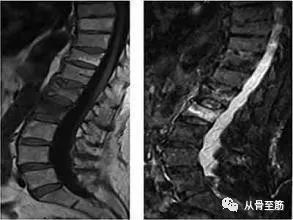

骨髓水肿这个名词,是随着磁共振成像(MRI)技术的应用而出现的,也就是说,只有在MRI检查中才能发现这种现象。病变区在MRI的T2WI压脂像上白,在T1WI上黑,与软组织水肿的影像学改变相似,故称为骨髓水肿。

其他影像检查不能够发现或诊断骨髓水肿(包括X线片、CT、超声等)。“骨髓水肿”并不是独立的疾病,只是某些疾病中的表现之一或某一阶段。就像关节腔积液不是一个独立疾病一样。外伤造成的骨髓水肿通常称为骨挫伤或隐匿性骨折,这是由于骨小梁的微骨折,引起局部的出血水肿和局部微细结构的改变。